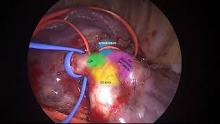

Subsequently, the inferior pulmonary ligament was identified and dissected carefully using LigaSure so that the left inferior pulmonary vein was adequately exposed. Then, also using LigaSure, the posterior mediastinal pleural reflection was freed. Isolation of the inferior pulmonary vein using a vascular sling was then performed. After this, the vascular sling was looped around the inferior pulmonary vein twice. Next, the pulmonary arteries were identified as per labeling. The same technique was applied for isolation of the interlobar pulmonary artery. A red vascular sling was gently looped around the interlobar pulmonary artery twice. It was important to perform this in a gentle manner because the pulmonary arteries are thin, fragile, and very close to each other. This step ensured a bloodless field upon exploration of basal segment pulmonary artery for the later retrieval of catheter fracture. Subsequently, the lingular pulmonary artery was isolated with a blue vascular sling.

After heparinization with 5,000 units of heparin, a vascular sling for the lingular pulmonary artery and interlobar pulmonary artery were tightened and reinforced by using Ligamax clips. This was performed using the same technique that was applied to inferior pulmonary vein. The basal segmental pulmonary artery was cut opened using a blade followed by scissors, and the pulmonary artery was inspected thoroughly but the fractured catheter was not found. The basal segmental pulmonary artery was then repaired using Prolene 5-0 sutures. It was a single layer continuous suturing, and the knotting was done with a knot pusher. It was then deaired by releasing the inferior pulmonary vein first before the pulmonary artery.

After the repair of the basal segmental pulmonary artery, a thorough inspection was performed. The tip of the fractured catheter was seen floating inside the lingular pulmonary artery. The catheter had migrated there during retraction of the lower lobe superiorly when the inferior pulmonary vein was isolated. Next, the V1–V3 pulmonary vein was isolated with a blue vascular sling, followed by the V4–V5 pulmonary vein using red vascular slings. These vessels were slung and tightened using Liga MX. The same technique was used as before. The tip of the catheter fracture could be seen from the thin wall of the lingular pulmonary artery. Subsequently, the lingular pulmonary artery was cut open using a blade. Back pressure of the blood pushed the catheter out immediately, and the catheter fracture was retrieved successfully.